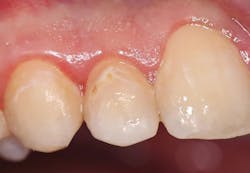

A 19-year-old female presented with a class II lesion on tooth no. 4. After local anesthesia, a conservative slot preparation was accomplished using a #330 pear-shaped carbide, and the remaining caries was removed with a slow-speed round bur (figure 3). A 1–1.5 mm enamel bevel was placed at a 45-degree angle on the occlusal and proximal margins with the very fine flame-shaped diamond (45u) to enhance the enamel etch and marginal seal. The preparation was isolated with a ring-based sectional matrix system (Palodent Plus, Dentsply/Sirona). A selective-etch technique of the enamel margins was employed, and the universal bonding agent was applied according to the DFU. Then, it was light cured for 20 seconds. Omnichroma was placed in two separate increments in the class II preparation, and then condensed and shaped with composite instruments. Each layer was exposed to the LED curing light for 20 seconds from the buccal, lingual, and finally, occlusal. After removal of the ring, wedge, and sectional matrix, the occlusion was checked in the usual manner, and shaping and polishing were completed using the same carbide burs and abrasive cup/point system as the class V restoration in case no. 1 (figure 4).Case no. 3